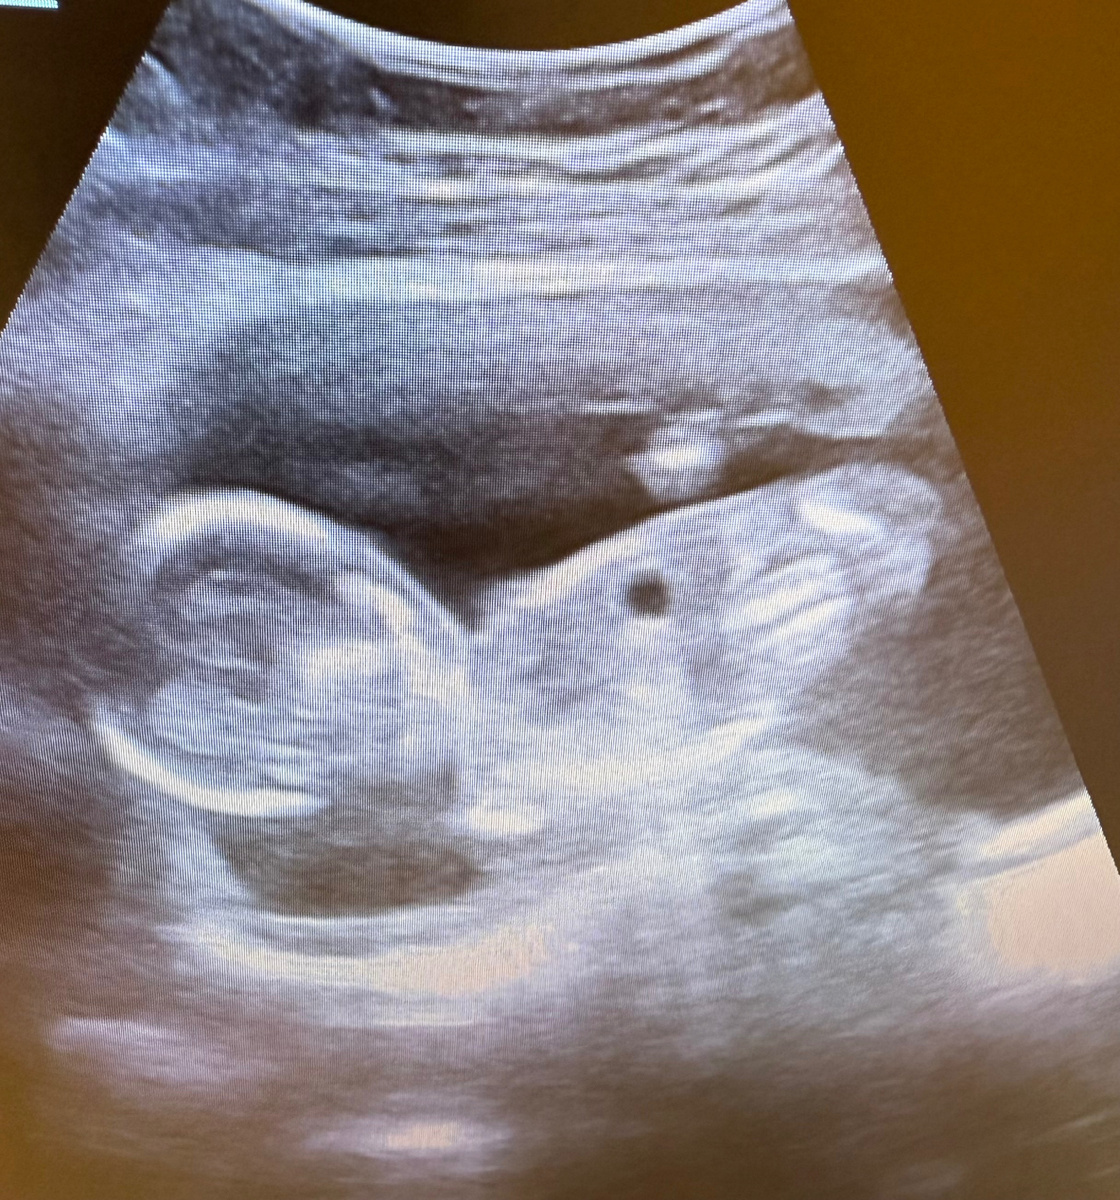

Беременность 18 недель. Фото из архива автора.

Чуть позже принесенное УЗИ подтвердило срок и поставило точку.